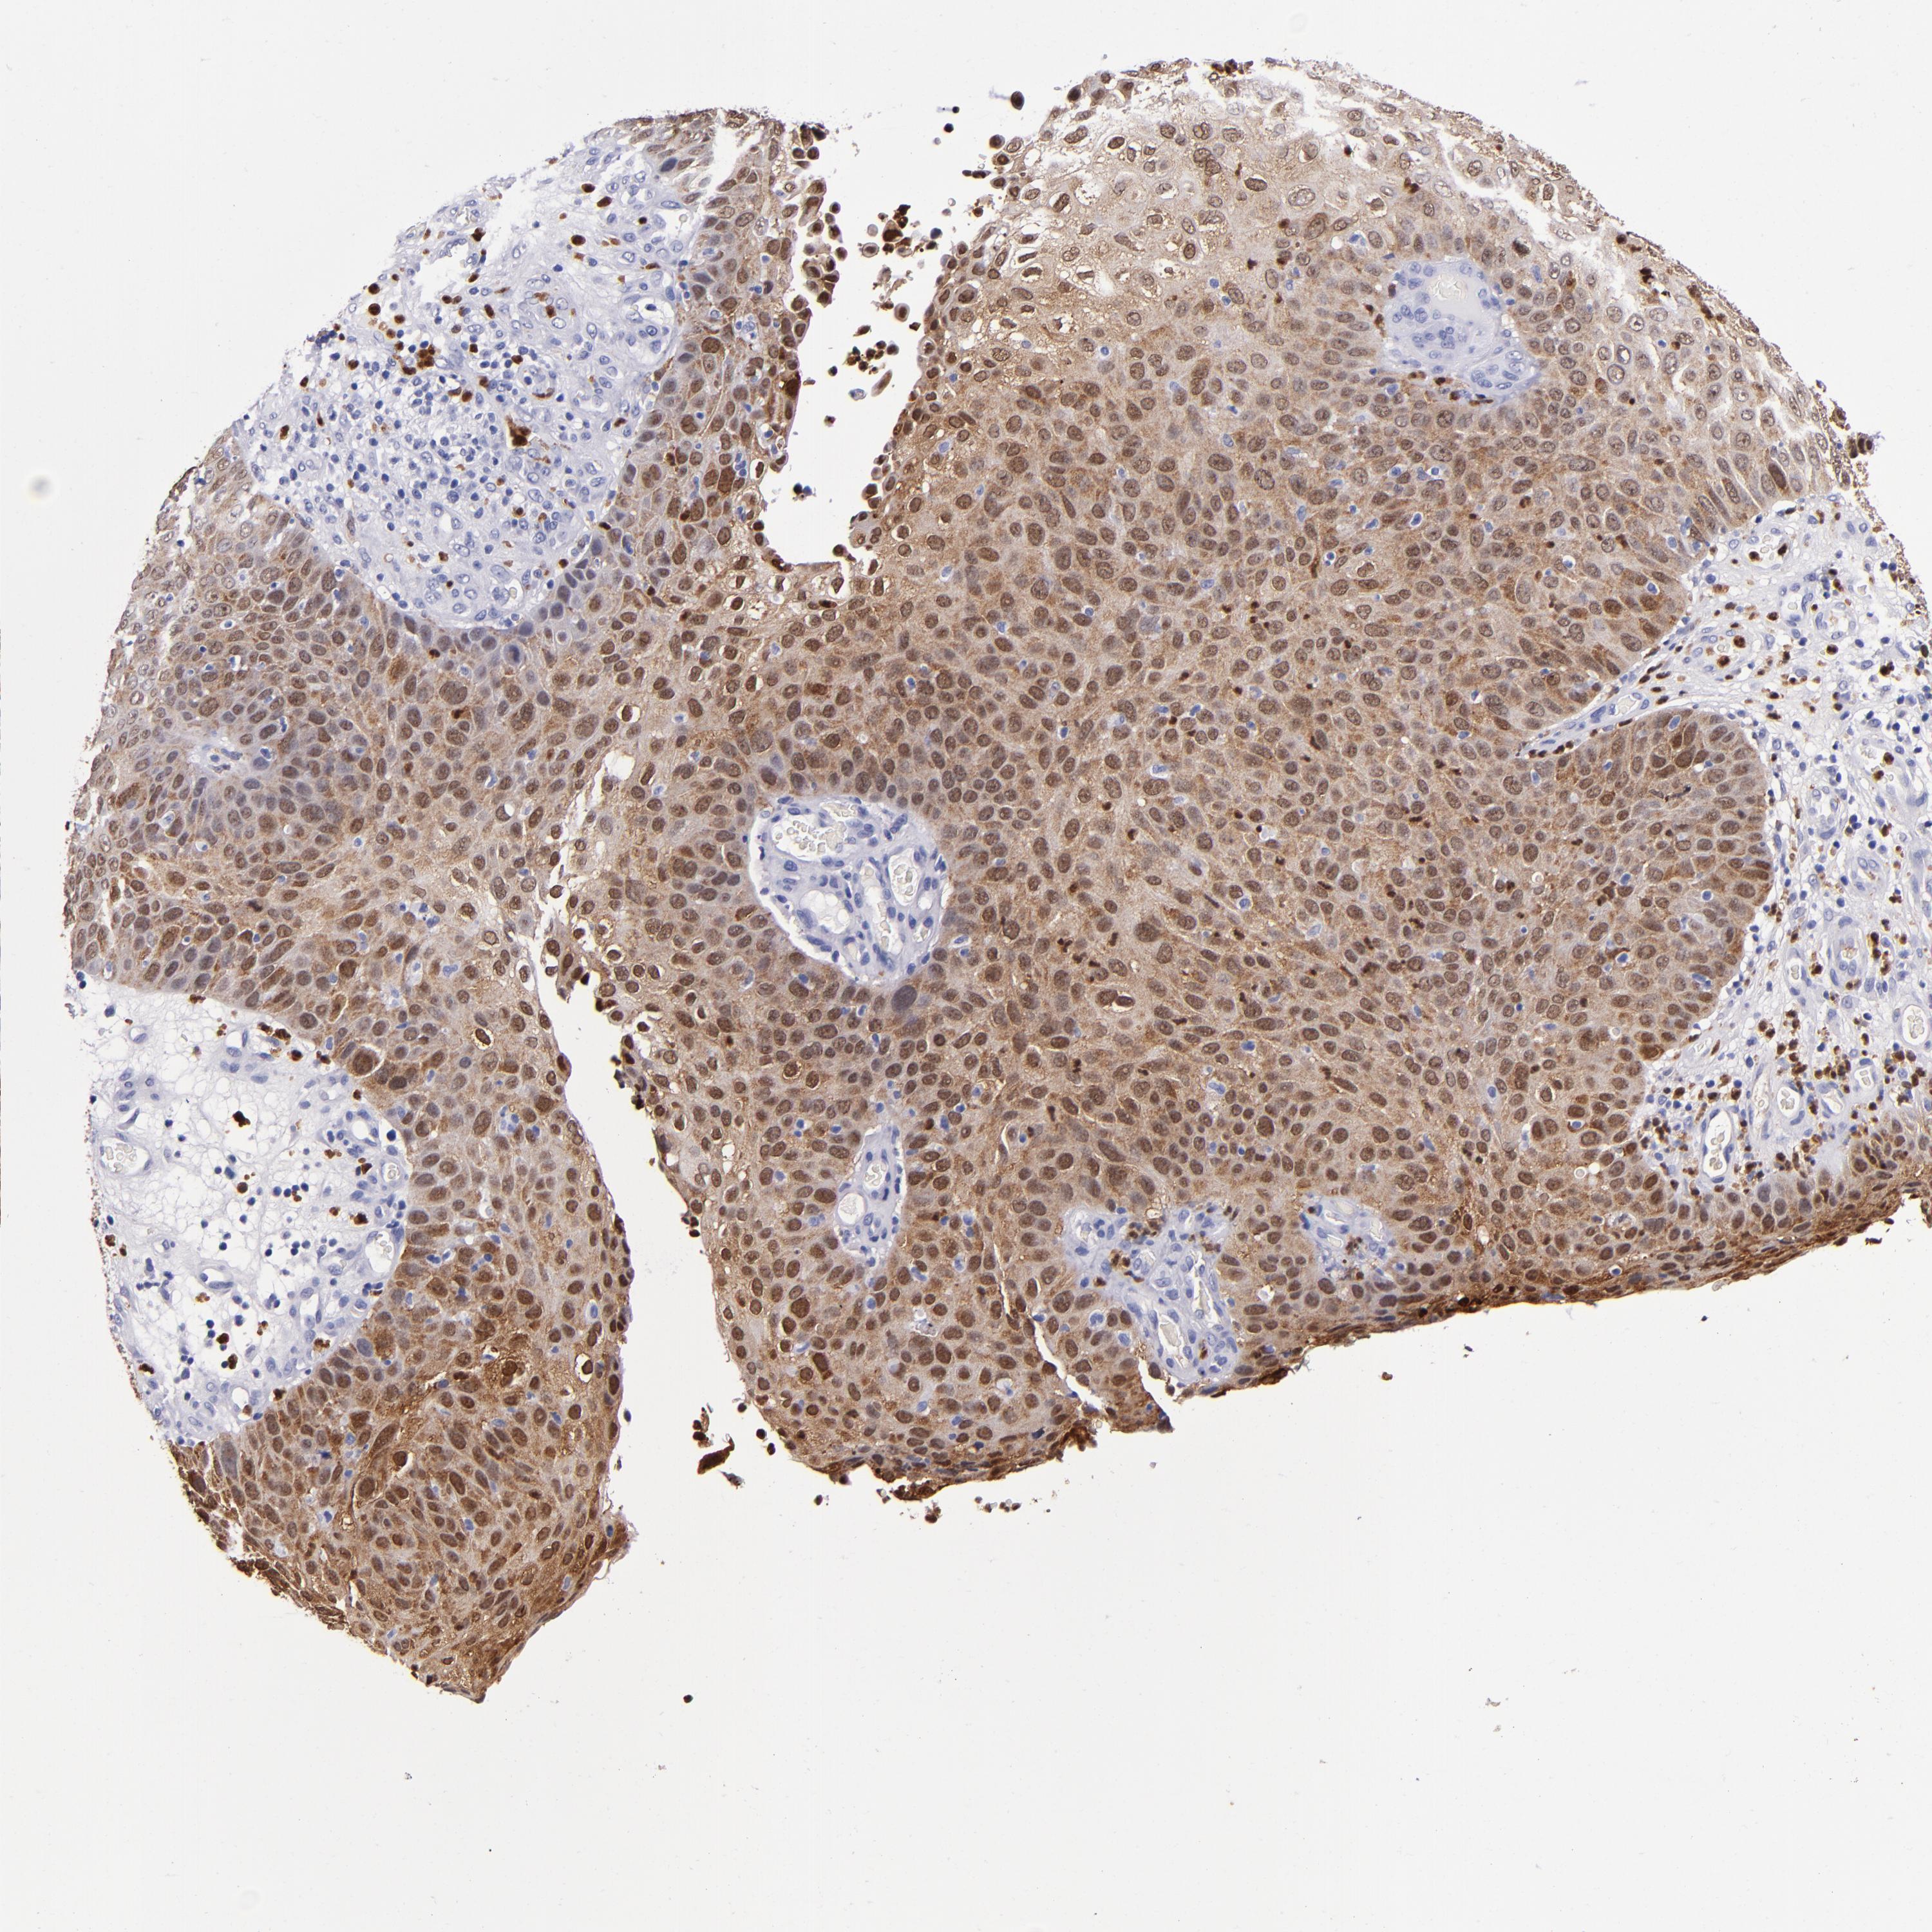

CANCER SKIN CANCER Show tissue menu

Basal cell and squamous cell cancer

SKIN CANCER - Protein expressioni

A mouse-over function shows sample information and annotation data. Click on an image to view it in a full screen mode. Samples can be filtered based on level of antibody staining by selecting one or several of the following categories: high, medium, low and not detected. The assay and annotation is described here.

Each image is clickable and will lead to virtual microscopy that enables deeper exploration of all samples and also displays staining intensity scores, fraction scores and subcellular localization as well as patient and tissue information for each sample.

Antibody HPA024372

Antibody CAB002791

Basal cell carcinoma

Squamous cell carcinoma, NOS

Squamous cell carcinoma, metastatic, NOS